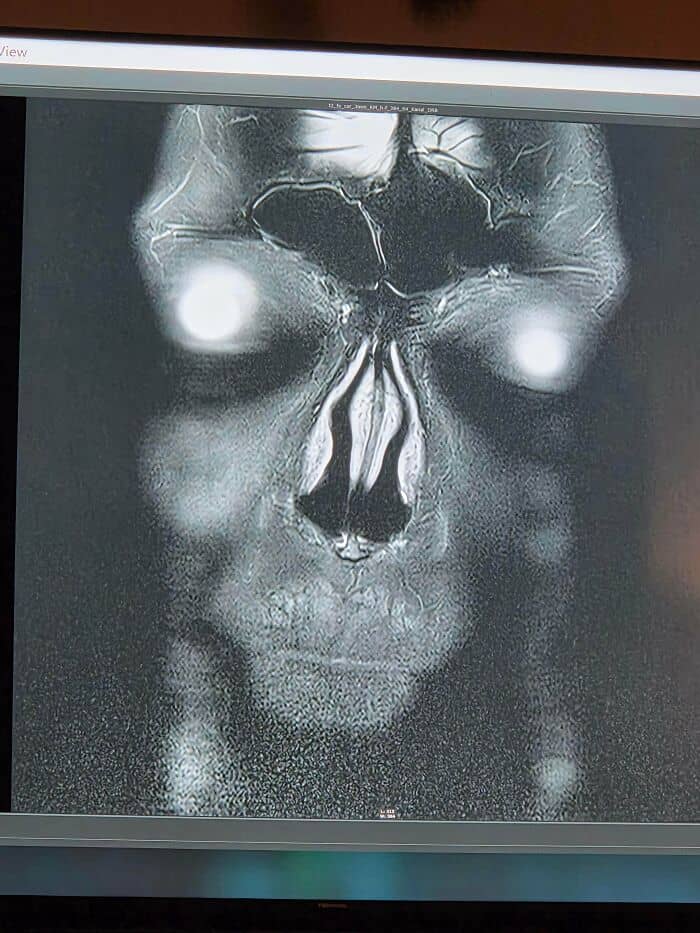

#52 My Mri Scan Results